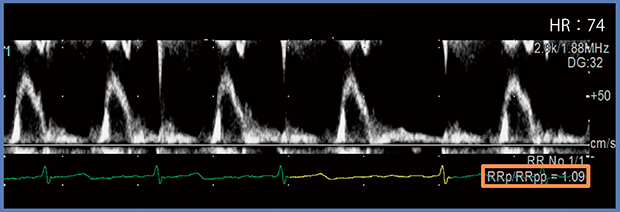

心房細動の不規則な心室興奮によって心拍ごとに左室駆出血流が異なる場合,計測する心拍の先行R-R(RRp)と先々行R-R(RRpp)がほぼ等しい区間を測定すると,1心拍で計測できることが知られている3)。従来,この先行R-R≒先々行R-Rとなる心拍は見た目で判断されてきたが,R-R間隔補正機能であるR-R Navigationを用いれば,先行R-Rと先々行R-Rの間隔がほぼ等しい,計測に最適な心拍が自動で検出される(図1)。画面右下(図1□)にはRRp/RRppの値が表示され,これが1に近いほど先行R-Rと先々行R-Rの間隔がより等しいということである。検出範囲は施設ごとに設定可能で,例えば±20%以内と設定すればRRp/RRpp 0.8〜1.2の心拍が選択される。

図1 R-R Navigationによる1心拍での先行R-Rと先々行R-Rの正確な計測